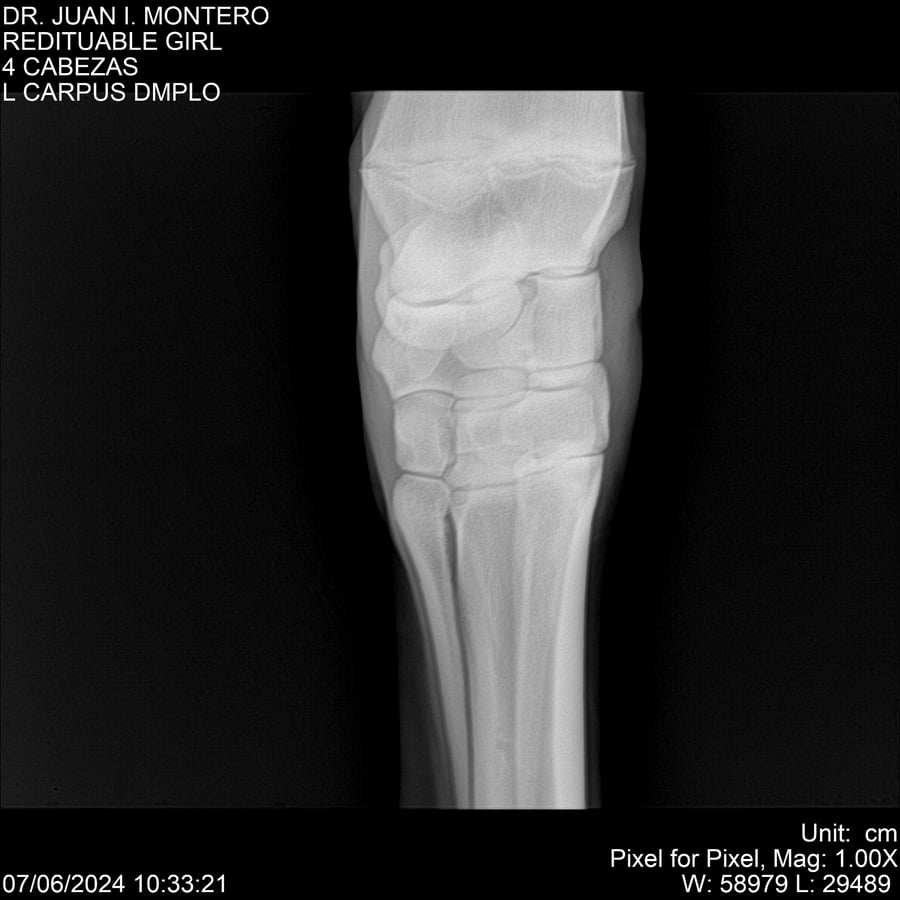

LOTE 19, REDITUABLE GIRL Lote Anterior Volver al remate Lote Siguiente Ficha Contacto Montevideo - Ficha del Lote Identificador: #281096 Categoría: Yeguarizos Montevideo - 79 Visualizaciones ClicData Contacto Empresa: Abelenda N. R., Walter Hugo Nombre*: Teléfono* : E-mail* : Mensaje Enviar Registrese gratis Este contenido Exclusivo está disponible sólo para usuarios registrados Ingresar